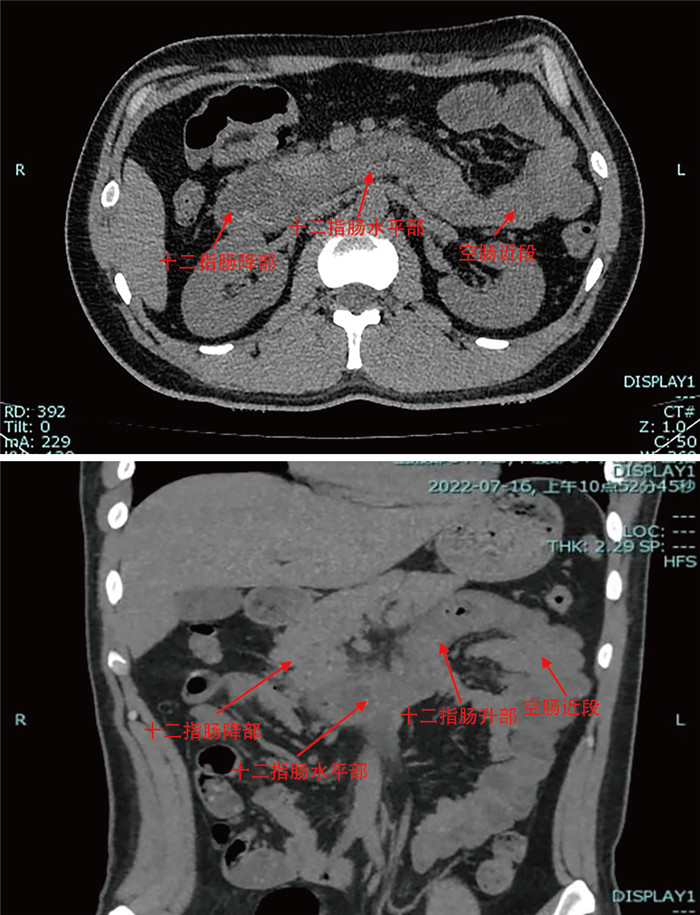

摘要:

通过回顾成人腹型过敏性紫癜误诊病例,分析原因并结合临床文献资料,总结腹型过敏性紫癜疾病特点,降低误诊率。本文回顾分析了2022年7月收治的1例被误诊为急性胃肠炎的成人腹型过敏性紫癜患者的临床资料,该例患者在腹痛后期出现皮肤紫癜,同时寻求多学科会诊,更改诊断为腹型过敏性紫癜,予以糖皮质激素、抗过敏药物等对症治疗后病情好转出院。腹型过敏性紫癜少见,而成人发病率更低,因缺乏特征性临床表现及特异性辅助检查,误诊率高,临床工作者应吸取经验教训,避免误诊错治。